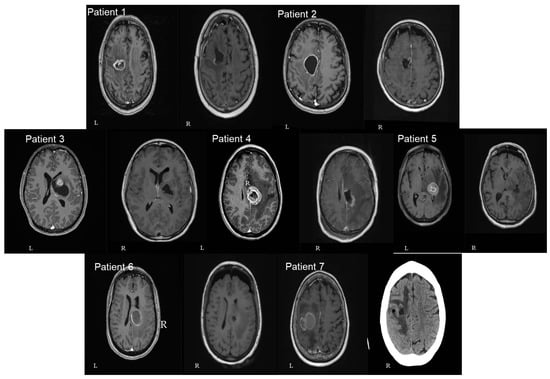

Figure 5.

Axial pre (left—L) and postoperative (right—R) T1 gad MRI brain images of all seven patients included in our study. A single axial view was selected in order to avoid confusion with multiple images. The number of patients in each image corresponds to the patients mentioned in Table 1 (patient number 7 had only postoperative CTH and no MRI available).

Gross total resection (GTR) was achieved in three patients, and near-total resection (NTR) in four patients (Figure 5). No ischemia was shown in the postoperative imaging and the range of cavity-to-CST distance was 0–4 mm.